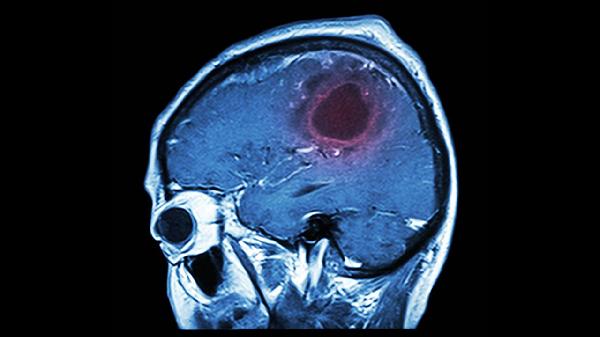

大脑就像一台精密仪器,需要细心呵护才能保持最.佳状态。但生活中一些看似不起眼的习惯,却可能在不知不觉中给大脑带来巨大伤害。脑溢血等严重问题往往不是突然发生的,而是日积月累的结果。了解这些潜在危险,及时调整生活方式,才能更好地保护我们的大脑。